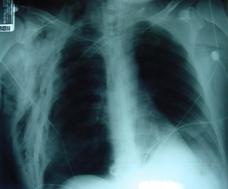

TRAUMATISME TORACICE

Emfizem subcutanat

Emfizem subcutanat Emfizem subcutanat

Aspect radiologic Imagine CT